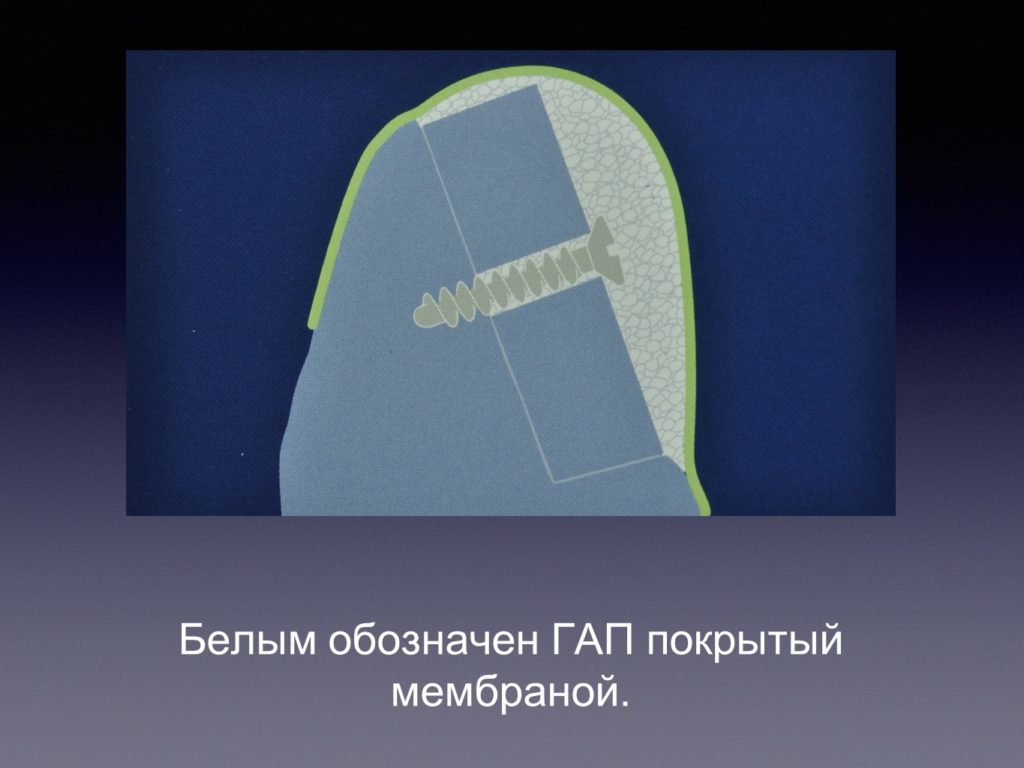

Принцип направленной костной регенерации. Костная регенерация под защитой мембраны Биоматрикс

Принцип направленной костной регенерации. Костная регенерация под защитой мембраны Биоматрикс

Принцип направленной костной регенерации. Костная регенерация под защитой мембраны Биоматрикс